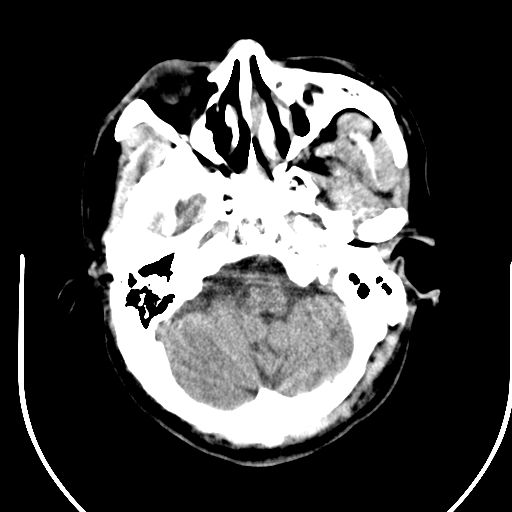

标题: CT25423:头部外伤意外发现右顶叶??? [打印本页]

标题: CT25423:头部外伤意外发现右顶叶???

ct值约13hu。

边缘清晰,没有占位效应,不像脑沟,结合ct值,软化灶可能吧

与脑沟没关系,小软化灶或陈旧性感染吧!

看样年纪不小了直接报腔梗,当然你要想报软化灶也是一样的

考虑右侧额叶巨腔隙灶;建议必要时行mri检查。